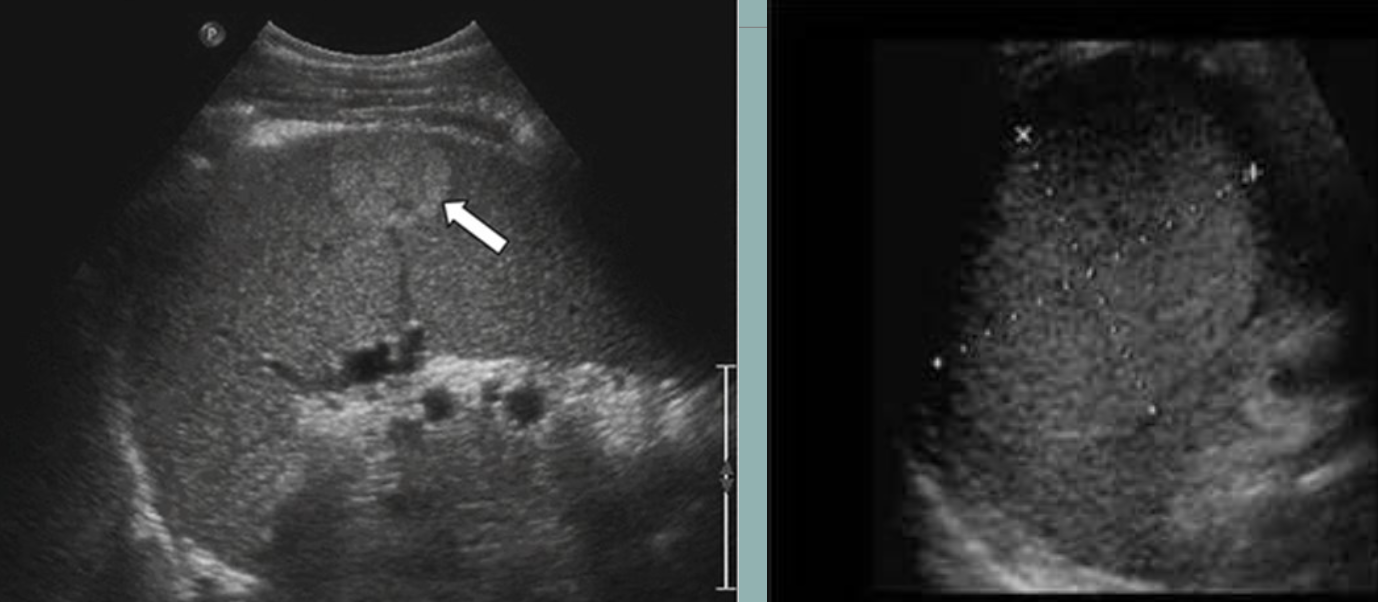

Hepatosplenic Candidiasis → severe systemic infection in those w/ weakened immune systems

clinical hx: immunocompromised (AIDS, chemo), fungal infection

s/sx: fever, abdominal pain, splenomegaly, nausea, anorexia

2D US: multiple hypoechoic abscesses, “bulls eye” sign (hypoechoic rim w/ echogenic core), hypoechoic ill-defined nodule, hyperechoic nodule

color doppler: avascular

DDX: splenic abscess (but usually solitary)